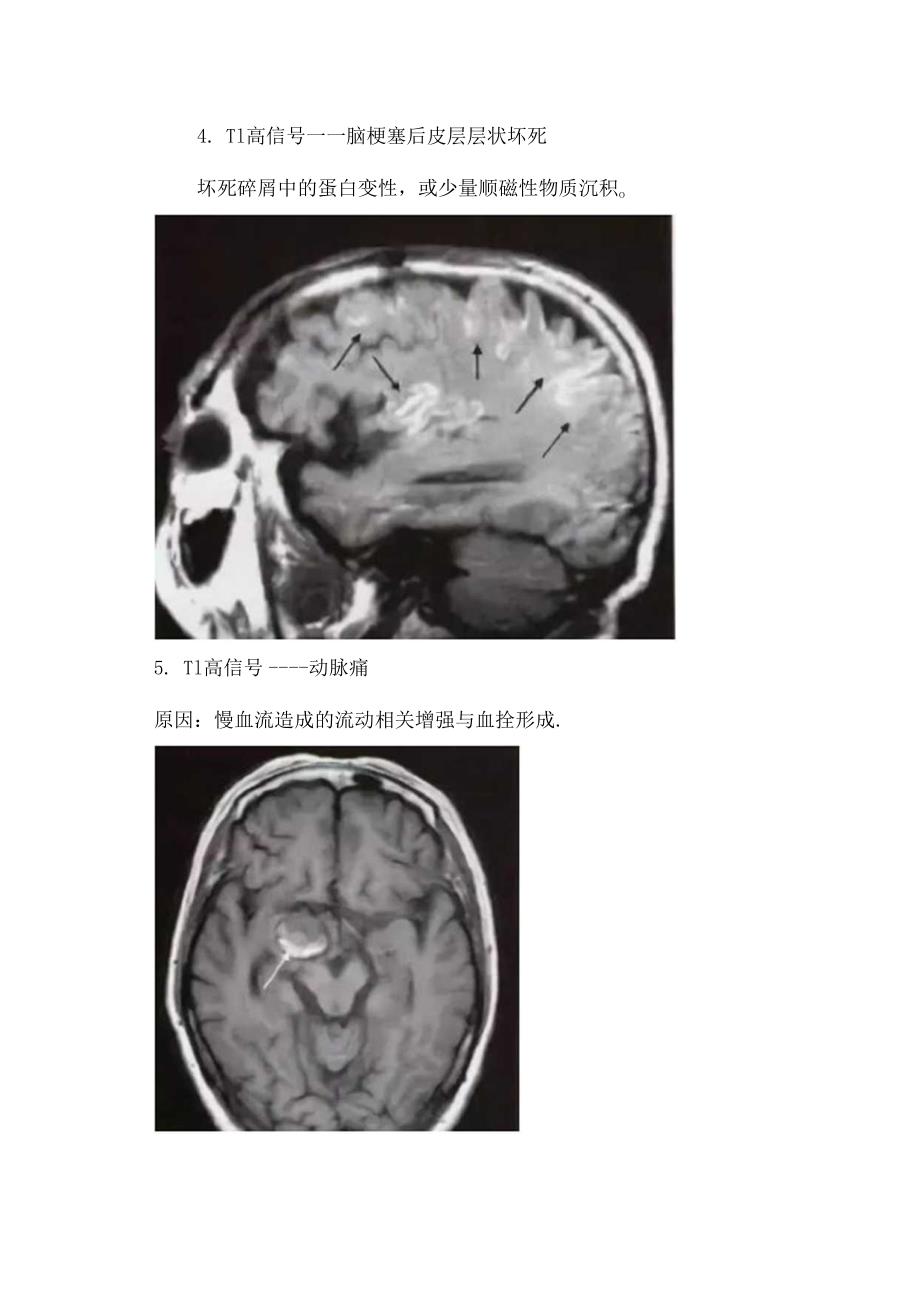

2、三为脂类分子。经典案例1.最常见的Tl高信号脂肪本例为肺胀体脂肪瘤。2、最常见的Tl高信号一一出血主要是高铁血红蛋白超强顺磁性作用导致。3.Tl高信号一一脑梗塞出血转化4. Tl高信号一一脑梗塞后皮层层状坏死坏死碎屑中的蛋白变性,或少量顺磁性物质沉积o5. Tl高信号动脉痛原因:慢血流造成的流动相关增强与血拴形成.7.Tl高信号动脉扩张迂曲8、TI高信号层面内血管在一定血流速度下,TlWI上呈高信号,由于TE明显延长,这些血管在T2WI呈流空信号。9. Tl高信号脑血管畸形脑血管畸形包括发育性静脉畸形、动静脉畸形、毛细血管扩张症、海绵状血管畸形。海绵状血管畸形常有慢性隐性出血,MRI为其首选影像学检查,典型表现为爆米花状高信号及病变周用含铁血黄素所致的信号环,但SWl比TIWl对出血更敏感。10. Tl高信号一一含蛋白物质下图为颅咽管瘤。下图为胶样囊肿。I1.Tl高信号一一肝性脑病镒过度沉积。黑色素的自由基含有不成对电子和氢质子的顺磁性效应。13.Tl高信号一一神经垂体抗利尿激素与血管加压素神经内分泌滤泡附近水分子弛豫增强。巨噬细胞吞噬脂质。15.Tl高信号钙化钙磁性钙盐+其他顺磁性物质;下图为软骨瘤。